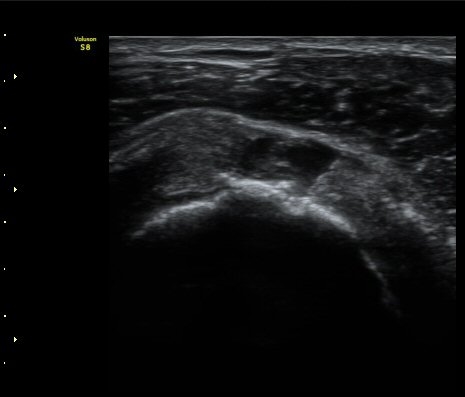

À̵ιڱ٠Á¾´Ü¸é°Ë»ç»ó ƯÀÌ ¼Ò°ßÀ» º¸ÀÌÁö ¾ÊÀ¸³ª(±×¸² 1)  ŽÃËÀÚ¸¦ ¾Æ·¡·Î À̵¿ÇÏ´Ï

°ß°©ÇÏ±Ù°Ç ³»Ãø¿¡¼­ ¼ö¾×Àú·ù°¡ °üÂûµÈ´Ù(±×¸² 2).